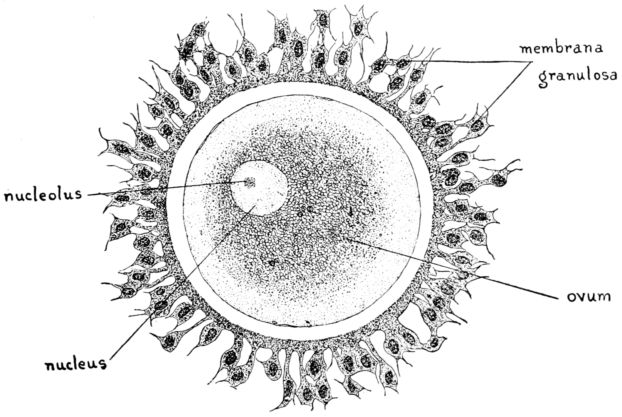

16. Diagram of human ovum 47

The ovary consists of two parts, the central part or medulla, composed of connective tissue, nerves, blood and lymph vessels, and the cortex, in which are embedded the vesicular Graafian follicles containing the ova. At birth each ovary contains upwards of 50,000 of these ova, which are the germ cells concerned with reproduction and the process of menstruation.